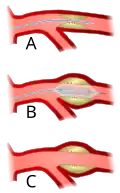

Perkutánní transluminální angioplastika (PTA) (perkutánní = vpichem přes kůži), zkráceně angioplastika, je chirurgický zákrok intervenční radiologie, při kterém je do postiženého místa zúžené cévy zaveden katétr, jenž má za cíl zvětšit průřez cévy, případně odstranit nebo porušit blokující aterosklerotické pláty. V závislosti na funkci katétru rozlišujeme balónkovou angioplastiku (cévy jsou roztahovány tlakem přes 100 metrů vodního sloupce, tj cca MPa) nebo laserovou angioplastiku. Obvykle je v místě zákroku implantován stent zamezující opětovnému zúžení cévy. Naprostá většina zákroků se provádí na srdečních tepnách při řešení hrozícího, nebo probíhajícího infarktu myokardu.

Po nalezení zúženého místa je zaveden balonek, který pod přibližně megapascalovým tlakem rozšíří průsvit tepny

Po nalezení zúženého místa je zaveden balonek, který pod přibližně megapascalovým tlakem rozšíří průsvit tepny -

Intervence může být zakončena umístěním stentu

Intervence může být zakončena umístěním stentu -